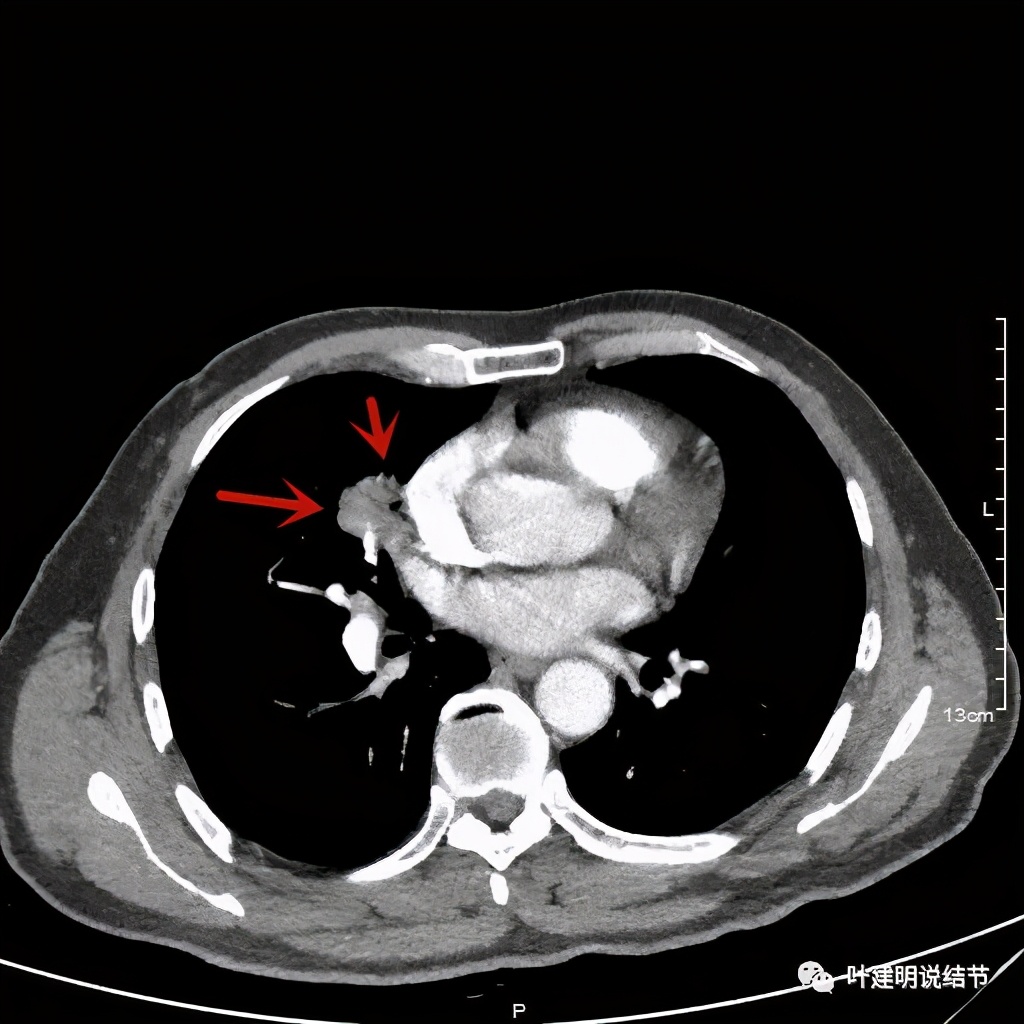

上图粉色箭头示细毛刺征,蓝色似支气管截断,红色示病灶膨胀性明显

纵隔窗分叶明显,密度不均

黄色箭头示病灶附近淋巴结或癌结节可能性大